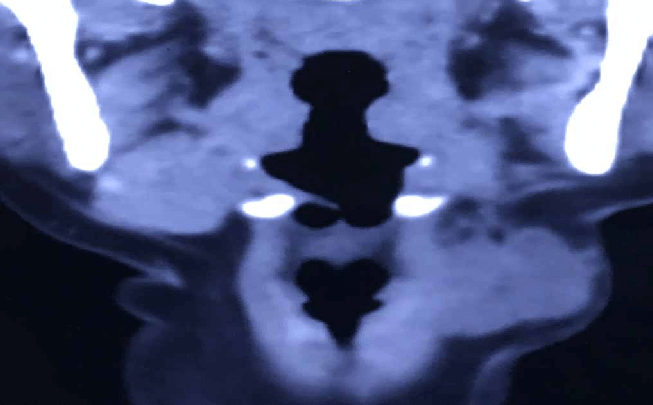

সিটি স্ক্যান বাম সাবম্যান্ডিবুলার অঞ্চলে একটি ভর ক্ষত দেখায় যা সাবকুটেনিয়াস প্লেন পর্যন্ত প্রসারিত হয়। ক্ষতটির এফএনএসি করা হয়েছিল যা প্লিওমরফিক অ্যাডেনোমা হিসাবে এসেছিল।